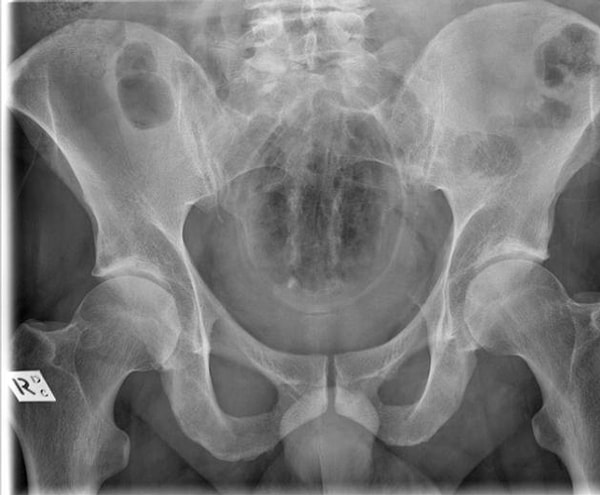

Итак, вашему вниманию предоставляются сами снимки. Попробуйте угадать, что там за предмет, если не сможете, то внизу есть подпись.

Банка с растворимым кофе.